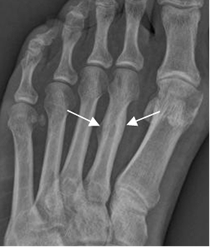

Fig 34. Fractura de stress.

Rx AP. Reacción perióstica en el tercio medio del 2º metatarsiano, por fractura de stress.